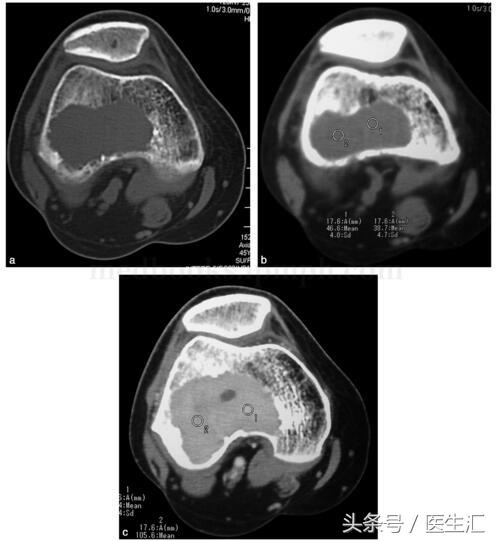

影像學(xué)檢查:X 線示右股骨遠(yuǎn)端骨端發(fā)生的一個(gè)偏心、基質(zhì)均勻、皮質(zhì)膨脹、皮質(zhì)無骨破壞、無骨膜反應(yīng)、無軟組織腫塊的溶骨性破壞(圖29‐1a,圖29‐1b)。CT 示右股骨遠(yuǎn)端骨端的溶骨性破壞,基質(zhì)均勻,注射造影劑后,病變強(qiáng)化,CT 值由強(qiáng)化前的40HU 增加到強(qiáng)化后的110HU(圖29‐2a~圖29‐2c)。

圖29‐2

a﹒CT 橫斷面示股骨外髁處溶骨性骨破壞(骨窗);

b﹒CT 橫斷面示股骨外髁處溶骨性破壞,CT 值為46HU(軟組織窗);

c﹒CT 橫斷面示增強(qiáng)CT 示腫瘤強(qiáng)化,CT 值達(dá)105HU